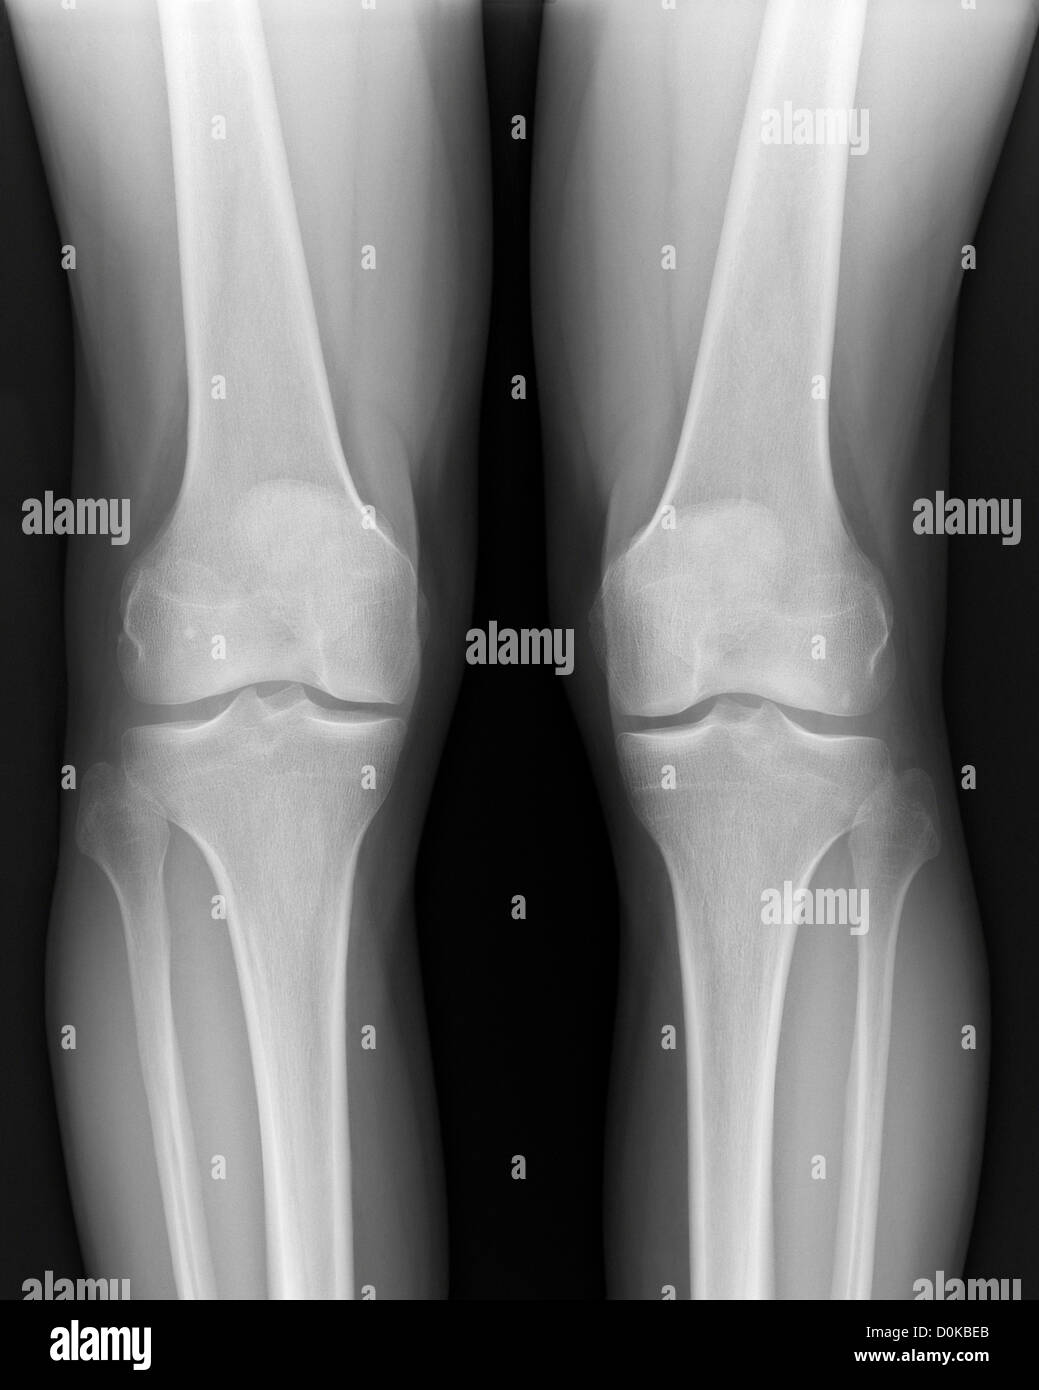

Ein xray menschlichen Beinen Knien Femur (oder Oberschenkelknochen Floating Kneecap Human The patella fits into a groove at the end of the femur (trochlear groove) and slides up and down as the knee bends and straightens. As you bend and straighten your knee, your kneecap moves up and down in. In a normal knee, the kneecap fits nicely in the groove. However, in a floating kneecap, the knee is displaced from. Floating Kneecap Human.